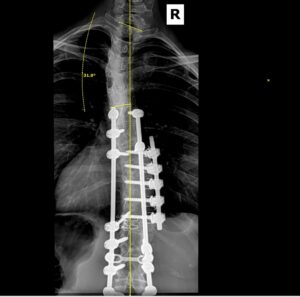

I was heartbroken. A fused spine meant I was done dancing. However, I was given a glimmer of hope as my surgeon decided to try a newer version of the surgery that would allow for more mobility than the typical method. For this procedure, the doctor removed one of my right ribs, deflated my right lung, fused several vertebrae, and inserted two titanium rods with screws to secure the curve.

After college I moved to the Seattle area for graduate school and went in for a regular annual x-ray to check my back. The curves above and below my fusion were much worse, and I was in constant pain. The treatment meant a second surgery as soon as possible. This time the surgeon opened my back and added fusions from vertebrae T4-L1 and more titanium rods and screws. The recovery was much easier the second time around and my pain subsided substantially.